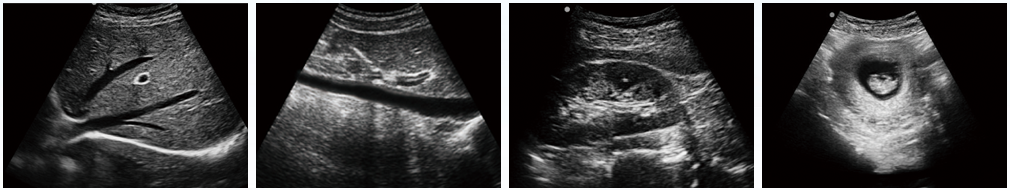

設備用途說明:主要應用于腹部、淺表組織、生殖系統、泌尿系統等器官的檢查